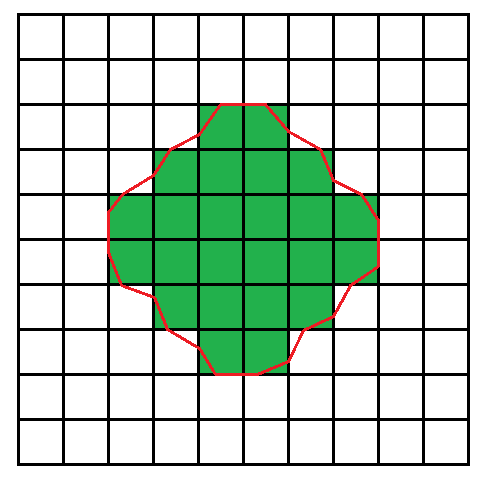

Сперва нужно получить границы согласно порогам, и для этого применяется алгоритм марширующих квадратов. Он, можно сказать, проходит в два этапа. Сначала область делится дискретной сеткой, и квадраты, значения интенсивности в которых больше или равны порогу, считаются “положительными”, остальные считаются “отрицательными”.

Каждый раз мы будем находится в каком-то узле, и нам необходимо очертить контур вокруг “положительных” квадратов. Для принятия решения мы будем рассматривать знаки четырех соседних квадратов: левый верхний, левый нижний, правый верхний, правый нижний. Если исключить симметрию, то нас интересует три случая.

Алгоритм марширующих квадратов точно и однозначно строит контур. В примере ниже я специально смещал линию от центра стороны, чтобы был отчетливо виден каждый шаг.